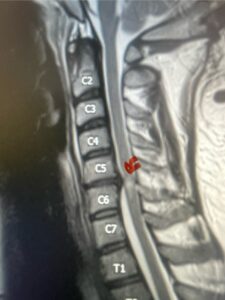

Fig. 3: Sagittal T2-weighted cervical MRI demonstrating a significant disc osteophyte complex causing spinal cord compression at C 5 6 with extensive myelomalacia (red arrow)

A 37-year-old male police officer complained of a one-month history of difficulty with his balance and leg weakness. He complained of achiness in his legs. He also complained of bilateral arm weakness and numbness of his hands. He was also having difficulty writing due to the weakness. Patient had an MRI of the cervical spine which demonstrated a disc/osteophyte at C56 causing spinal cord compression and concurrent myelomalacia (Fig. 3). Patient underwent an anterior cervical discectomy with a cage and plate (Fig. 4). He tolerated the procedure well with improved numbness and weakness. This is a young person with fairly extensive myelomalacia and a fairly rapid development of symptoms. For this it was felt surgery was indicated. How he will do will depend on how much of his symptoms was caused by the compressive component or intrinsic damage to the spinal cord. As a rule, patients generally improve to some extent quickly; but their recovery of their spinal cord function can sometimes take up to 2 years to realize the extent of their improvement. Patients have to be patient with themselves in terms of their expected recovery.